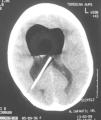

Pruebas complementarias: radiografía lateral de cráneo (fig. 1): neumoencéfalo en los ventrículos laterales (neumoventrículo) y VDVP. TC de cráneo (fig. 2): neumoventrículo con dilatación de los ventrículos laterales y VDVP.

La TC es una técnica diagnóstica muy sensible para realizar el diagnóstico y se considera el método de imagen de elección6 ya que es capaz de detectar cantidades de hasta 0,5ml de aire en la cavidad intracraneal7. En esta prueba el aire se observa como una imagen hipodensa redondeada, rodeada de parénquima cerebral normal. Un signo radiológico que ayuda a diagnosticar un neumoencéfalo a tensión es el signo de Monte Fuji, descrito como un ensanchamiento del espacio interhemisférico entre los lóbulos frontales8. En nuestro caso, el diagnóstico se hizo con una radiografía de cráneo solicitada dentro del estudio del trayecto de la VDVP.